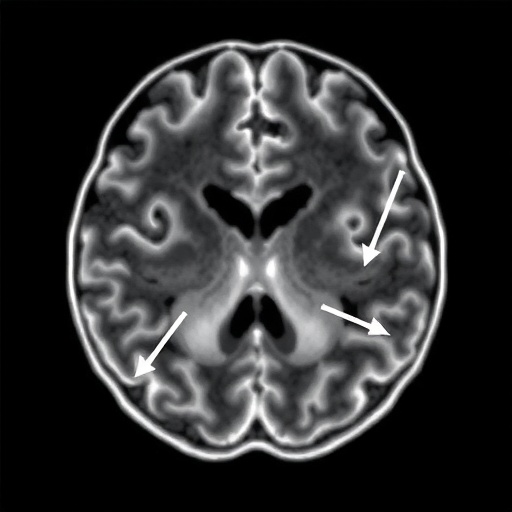

Diving deeper into the technicalities of the study, the researchers observed that it isn’t just the absolute speed of blood but the asymmetry of velocities across the brain’s hemispheres that provides the most definitive clues. In many cases of Moyamoya, the disease progresses unevenly, creating a hemodynamic imbalance that further stresses the fragile “puff of smoke” vessels. The study’s data indicates that when one side of the brain shows a dramatic spike in velocity compared to the other, the risk of a localized stroke or “silent” infarct increases exponentially. This nuanced understanding of intracranial hemodynamics allows for a more personalized approach to medicine, where treatment plans are tailored to the specific flow patterns of an individual’s brain rather than a one-size-fits-all protocol based on general age or symptom presentation.